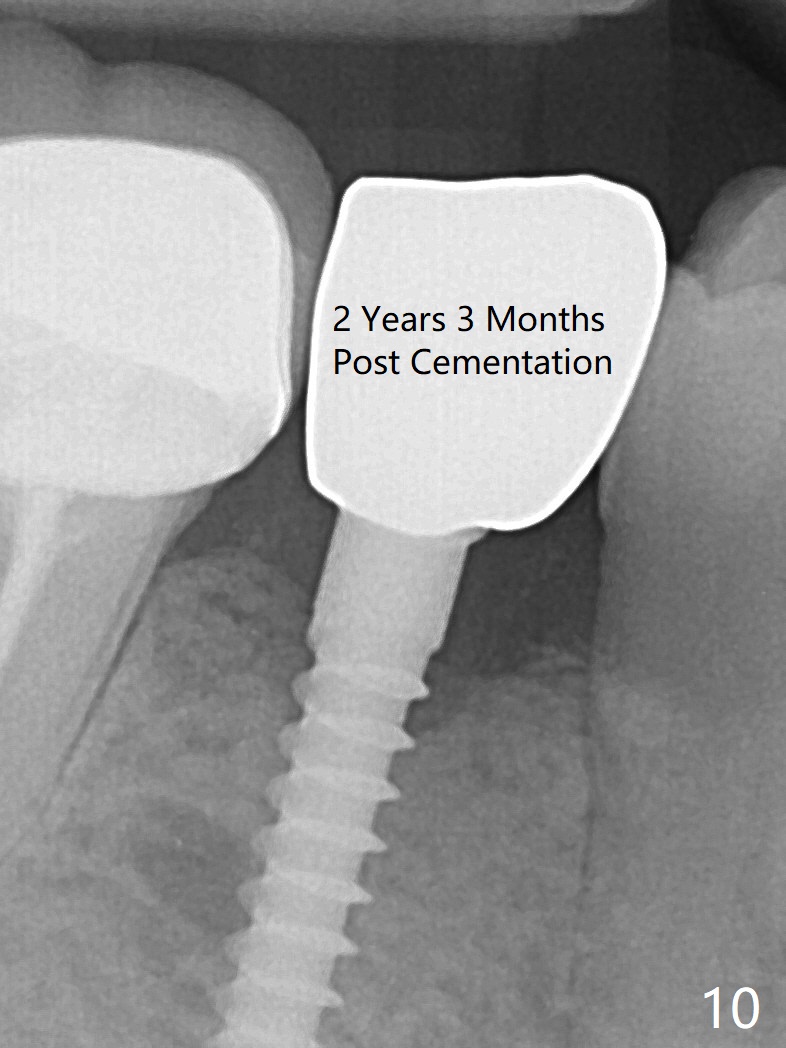

Preop photo shows the distal inclination of the tooth #28 (Fig.1). The distal surface of the latter is reduced before incision for implant placement at #29 (Fig.2). The buccolingual width is approximately 4 mm, as compared to 3 mm implant positioner (Fig.3). After 1.2x10 mm osteotomy (Fig.5), the mesiodistal cortical bone is removed with a small high-speed fissural bur (Fig.4). When a 2.5x12(2) mm 1-piece implant is placed (Fig.6), there is no buccal (Fig.7) or lingual plate perforation. There is no postop paresthesia. There is mild bone loss distal 4 months postop (Fig.8 *). Take photos before and after permanent crown cementation to show increase in ridge width after bone graft and improvement in gingival health after provisional modification. Take PA and/or BW post cementation to show that the distal bone resorption (Fig.8 *) is partially due to angulation. No continuous bone loss 15 months post cementation (Fig.9). There is mild bone resorption mesially 2 years 3 months post cementation (Fig.10). The soft and hard tissues remain healthy 4 years 3 months post cementation (Fig.11,12).